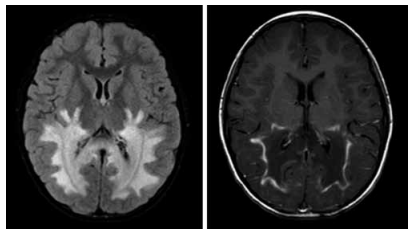

Menina de 9 anos de idade apresenta história progressiva de distonia, disartria e regressão cognitiva. A imagem por ressonância magnética de crânio revela o achado a seguir.

O gene mais provavelmente associado ao quadro é: